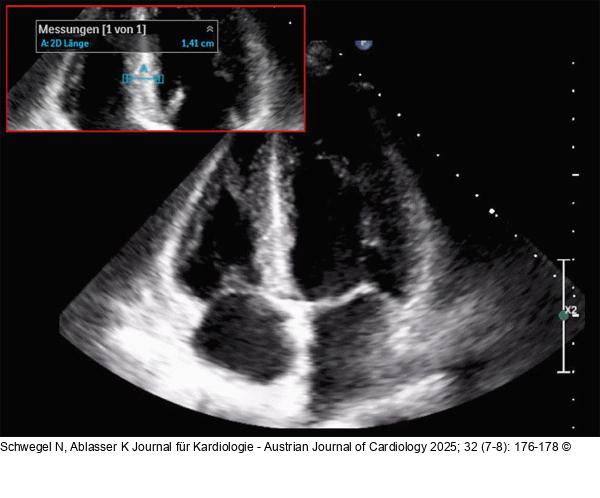

Abbildung 1: Echokardiographie Echokardiographie bei Erstvorstellung |